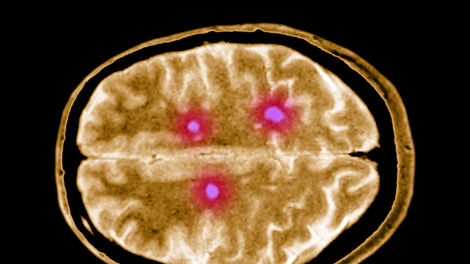

Objave z oznako "multipla skleroza"

Ta virus bi lahko bil sprožilec multiple skleroze (in zdaj znanstveniki o tem vedo nekaj več)

Multipla skleroza: le redki slovenski bolniki imajo dostop do celostne obravnave

Zahrbtna neozdravljiva bolezen, ki prizadene živčni sistem: zanjo trpi več tisoč Slovencev

Slovenskim bolnikom z multiplo sklerozo na voljo novo biološko zdravilo

Svetovni dan multiple skleroze: letošnja tema je povezovanje za boljšo zdravstveno oskrbo

Multipla skleroza: "Vesel sem, da si sam umivam zobe …" (resnične zgodbe Slovencev)

7 zgodnjih znakov multiple skleroze (pojavijo se lahko že pri dvajsetih!)

Presaditev matičnih celic bi lahko bila revolucionarna za obolele z multiplo sklerozo